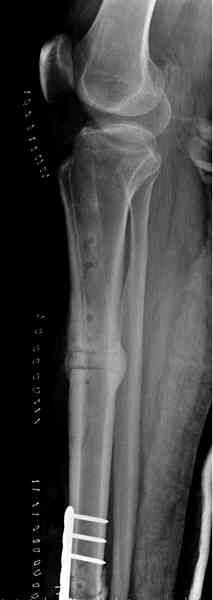

Оперирован в военном госпитале с заменой сегмента аллокостью

большеберцовой кости и после демобилизации явился для постоянного

наблюдения по месту жительства.

Наши имели проблему со сращением, пришлось им сделать динамизацию,

дополнительную аутопластику.

Снимки представлены.

Имя     : 4 adamantioma ap.jpg